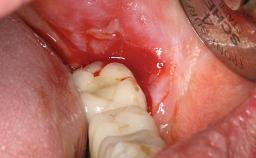

A 35-year old female patient was referred to the Department of Oral Surgery and Stomatology at the University of Bern, Switzerland, for examination of an implant site that had exhibited clinical signs of slightly delayed wound healing. In addition, the referring clinician found no evidence for a facial bone wall when she raised a flap to gain access to the implant for abutment connection. Four months earlier, she had inserted a bone-level implant in a single-tooth gap, where the lateral incisor had been extracted due to a chronic periapical lesion on the mesial aspect of the root. Implant placement was combined with simultaneous bone augmentation using deproteinized bovine bone mineral (DBBM, Bio-Oss®; Geistlich, Wolhusen, Switzerland) and a collagen membrane (Bio- Gide®; Geistlich), followed by primary wound closure. The patient also provided the postsurgical radiograph that displayed the implant with a 3.5-mm healing cap.